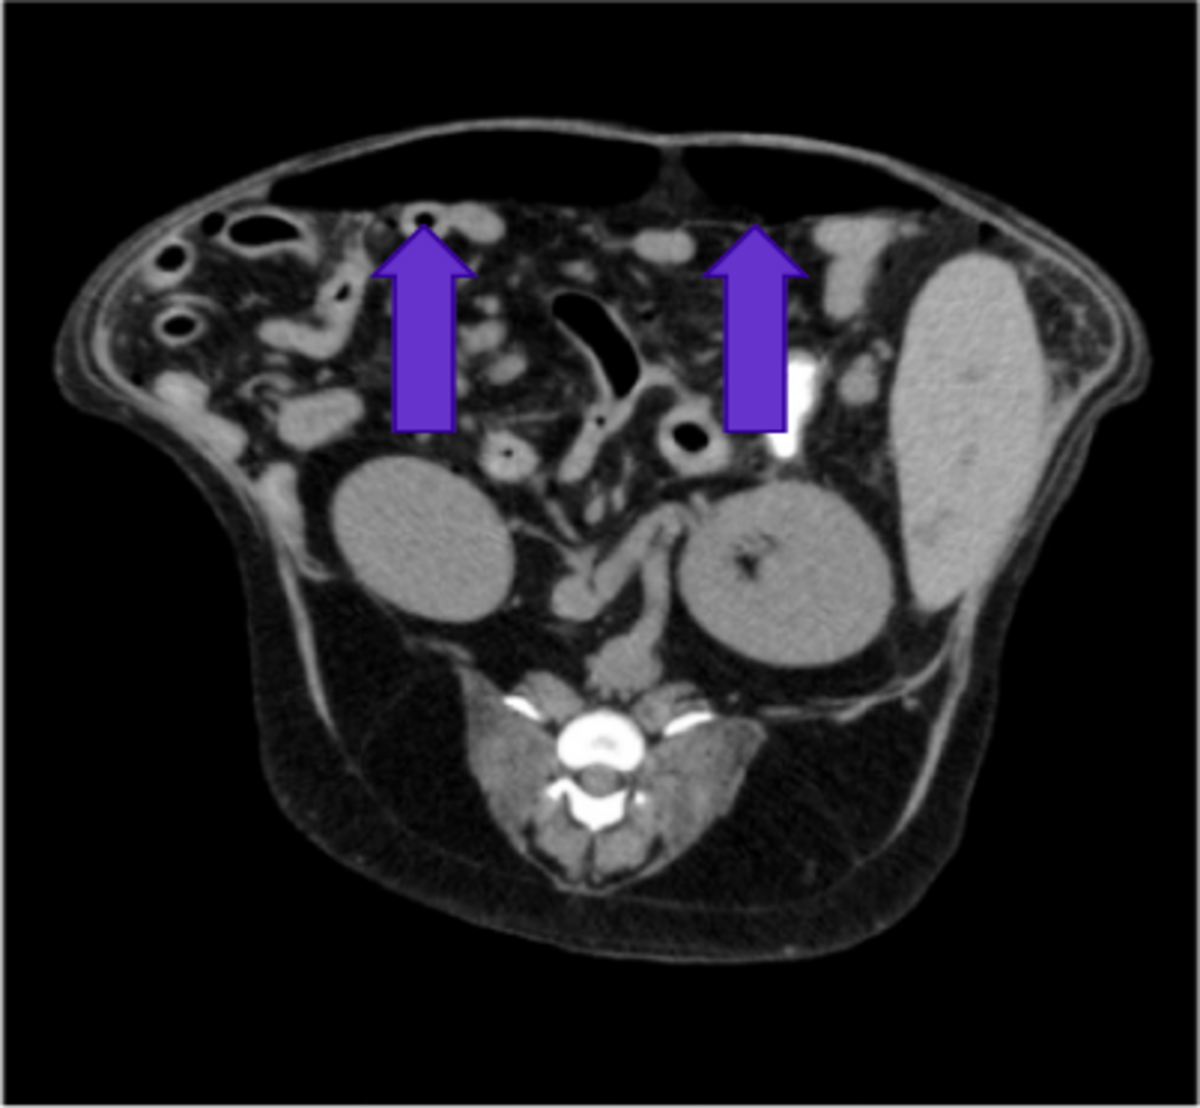

画像診断:腹部X線検査、エコー検査、CT検査による腹部の液体貯留および遊離ガス像の確認(図1)

図1:CT検査による腹腔内遊離ガスの確認

CT検査では、レントゲン同様、腹腔内に遊離ガス像が確認されました。さらに、試験開腹では十二指腸・空腸移行部に穿孔が確認されたため(図6)、穿孔部位の腸管を切除し端々縫合を行いました。